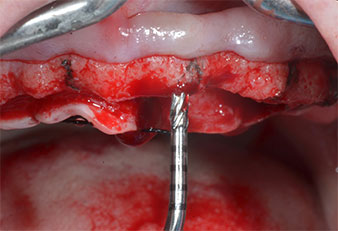

Abb. 2: Nach dem Kieferkammschnitt und der Präparation der Mukoperiostlappen werden die Implantatpositionen auf den Knochen übertragen.

Ein flammenförmiges, diamantiertes piezochirurgisches Instrument (Piezomed I1) wurde verwendet, um die Implantatpositionen zu markieren und die Pilotpräparationen durchzuführen (Abb. 3). Dabei wurde darauf geachtet, eine Auf- und Abbewegung mit reduzierter Leistung, voller Spülung und niedrigem Druck (unter 300 g) anzuwenden. Als Nächstes wurde ein Pilotinstrument (Piezomed I2A/I2P) zur initialen Erweiterung der Implantatlager auf einen Durchmesser von 2 mm verwendet (Abb. 4), gefolgt von einem 3-mm-Instrument (Abb. 5).

Abb. 3: Die Präparation mit dem Ultraschallmarkerinstrument Piezomed I1 erfolgt mit einer Auf- und Abbewegung, parallel zur Längsachse des Arbeitsteils.